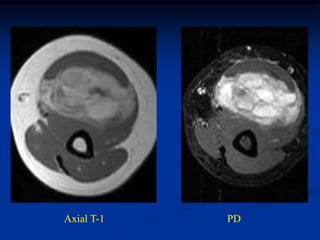

Case #261

62 year female

MFH anterior thigh

AP x-ray

Sagittal proton

density MRI

Sagittal T-2 MRI

Axial proton density MRI

Axial T-2 MRI